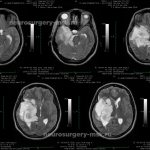

КТ: виды, противопоказания, как проходит

КТ (компьютерная томография) – это метод диагностического обследования организма. Инструментальный тест проводится с применением